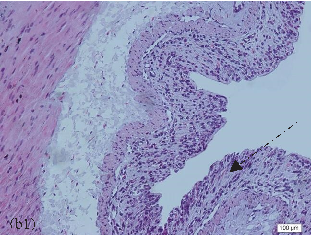

- FIGURE 2: Histopathological analysis of the colon related tothe experimental group: control group(a, a1), colitis group (b, b1),andN-acetylcysteine (NAC) group (c, c1). Representative photomicrographs of mouse colonic sections. Black arrow, preservation of the crypt structure; black dashed arrow, crypt destruction; and black dotted arrow, narrowing of the mucosal muscle. 10x magnification. Hematoxylin and eosin (HE) staining.

- 3.1. Histological Analysis of the Colon. Histological evaluation showed changes in colon architecture related to colitis, including destruction, disarrangement, and shortening of the crypts, indicating that the administration of DSS induced UC in mice (Figure 2(b)), when compared to the control (Figure 2(a)). NAC administration partially restored the epithelial structure, as indicated by the intact areas in the histological section (Figure 2(c)).